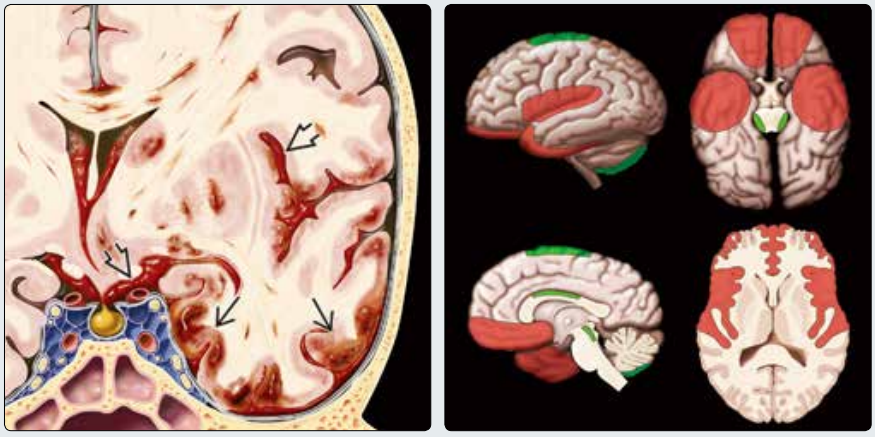

(左图)冠状位示意图为闭合性颅脑损伤的病理表现。注意出血点累及多处脑回的灰质→,轴索及深部灰质损伤,创伤性蛛网膜下腔出血➪中位于基底池及外侧裂

(右图)图示红色为脑挫伤最常见的部位。绿色为较罕见的部位。最常见部位为额叶前下部及颞叶前下部